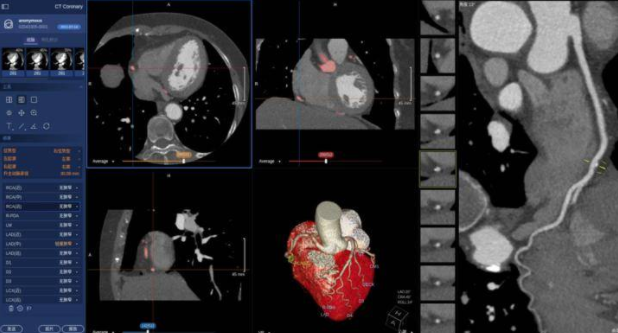

4.视觉诊断

视觉诊断包含两个部分,一个是诊断机器,一个诊断生物。

传统的工业诊断方法是人拿工具到现场检查,诊断机器的目标是通过视觉分析的手段能够代替人工对机器的检查。通过现场拍摄录像,通过视觉分析的手段,能够自动的诊断出机器的故障;诊断生物则是医学影象智能诊断。